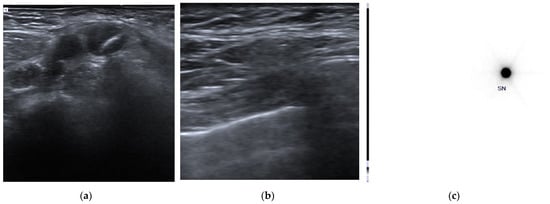

Patients who did not undergo surgical treatment after NACT (the discovery of M1-disease during NACT) or who underwent surgery at another institution (14 out of 104 patients, 13.5%), those who discontinued NACT (3 out of 104 patients, 2.9%), and those who did not undergo the ROLL procedure used to identify clip-marked lymph nodes due to patient refusal (6 out of 104 patients, 5.8%) or did not complete the intended protocol due to other reasons (4 out of 104 patients, 3.8%) were excluded. In 5 out of 77 patients (6.5%), the clip was not sonographically identified, and the ROLL procedure was not performed. For all these patients, ALND was performed, with residual nodal disease observed in two patients. In the remaining 72 procedures (72/77, 93.5%), the ROLL node injection was performed under US guidance (Figure 1).

Figure 1. Clip placement and pre-surgical identification of clipped axillary lymph node. (a) A clip marker was placed within the cortex of the histologically confirmed metastatic axillary lymph node (clipped lymph node, CLN) before the beginning of neoadjuvant chemotherapy. (b) Before surgery, an US axillary evaluation was performed to identify the CLN and a radioactive tracer—Technetium 99mTc macro-aggregated albumin (99mTc-MAA)—was injected into the CLN under US guidance using a 21G needle. (c) Pre-surgical scintigraphic acquisition shows the presence of focal activity in the tracer inoculation site.